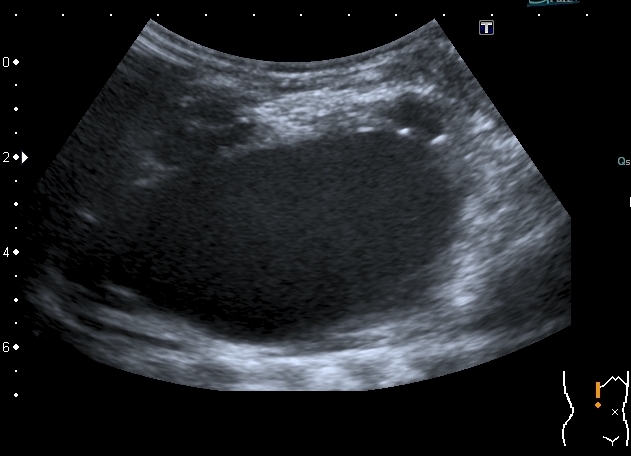

Тему уже давно закрыли, но вот свежая "красивая" картинка; левая почка незначительно увеличена в размерах, без изменений ЧЛС, со слов больного он уже несколько лет наблюдается у уролога: